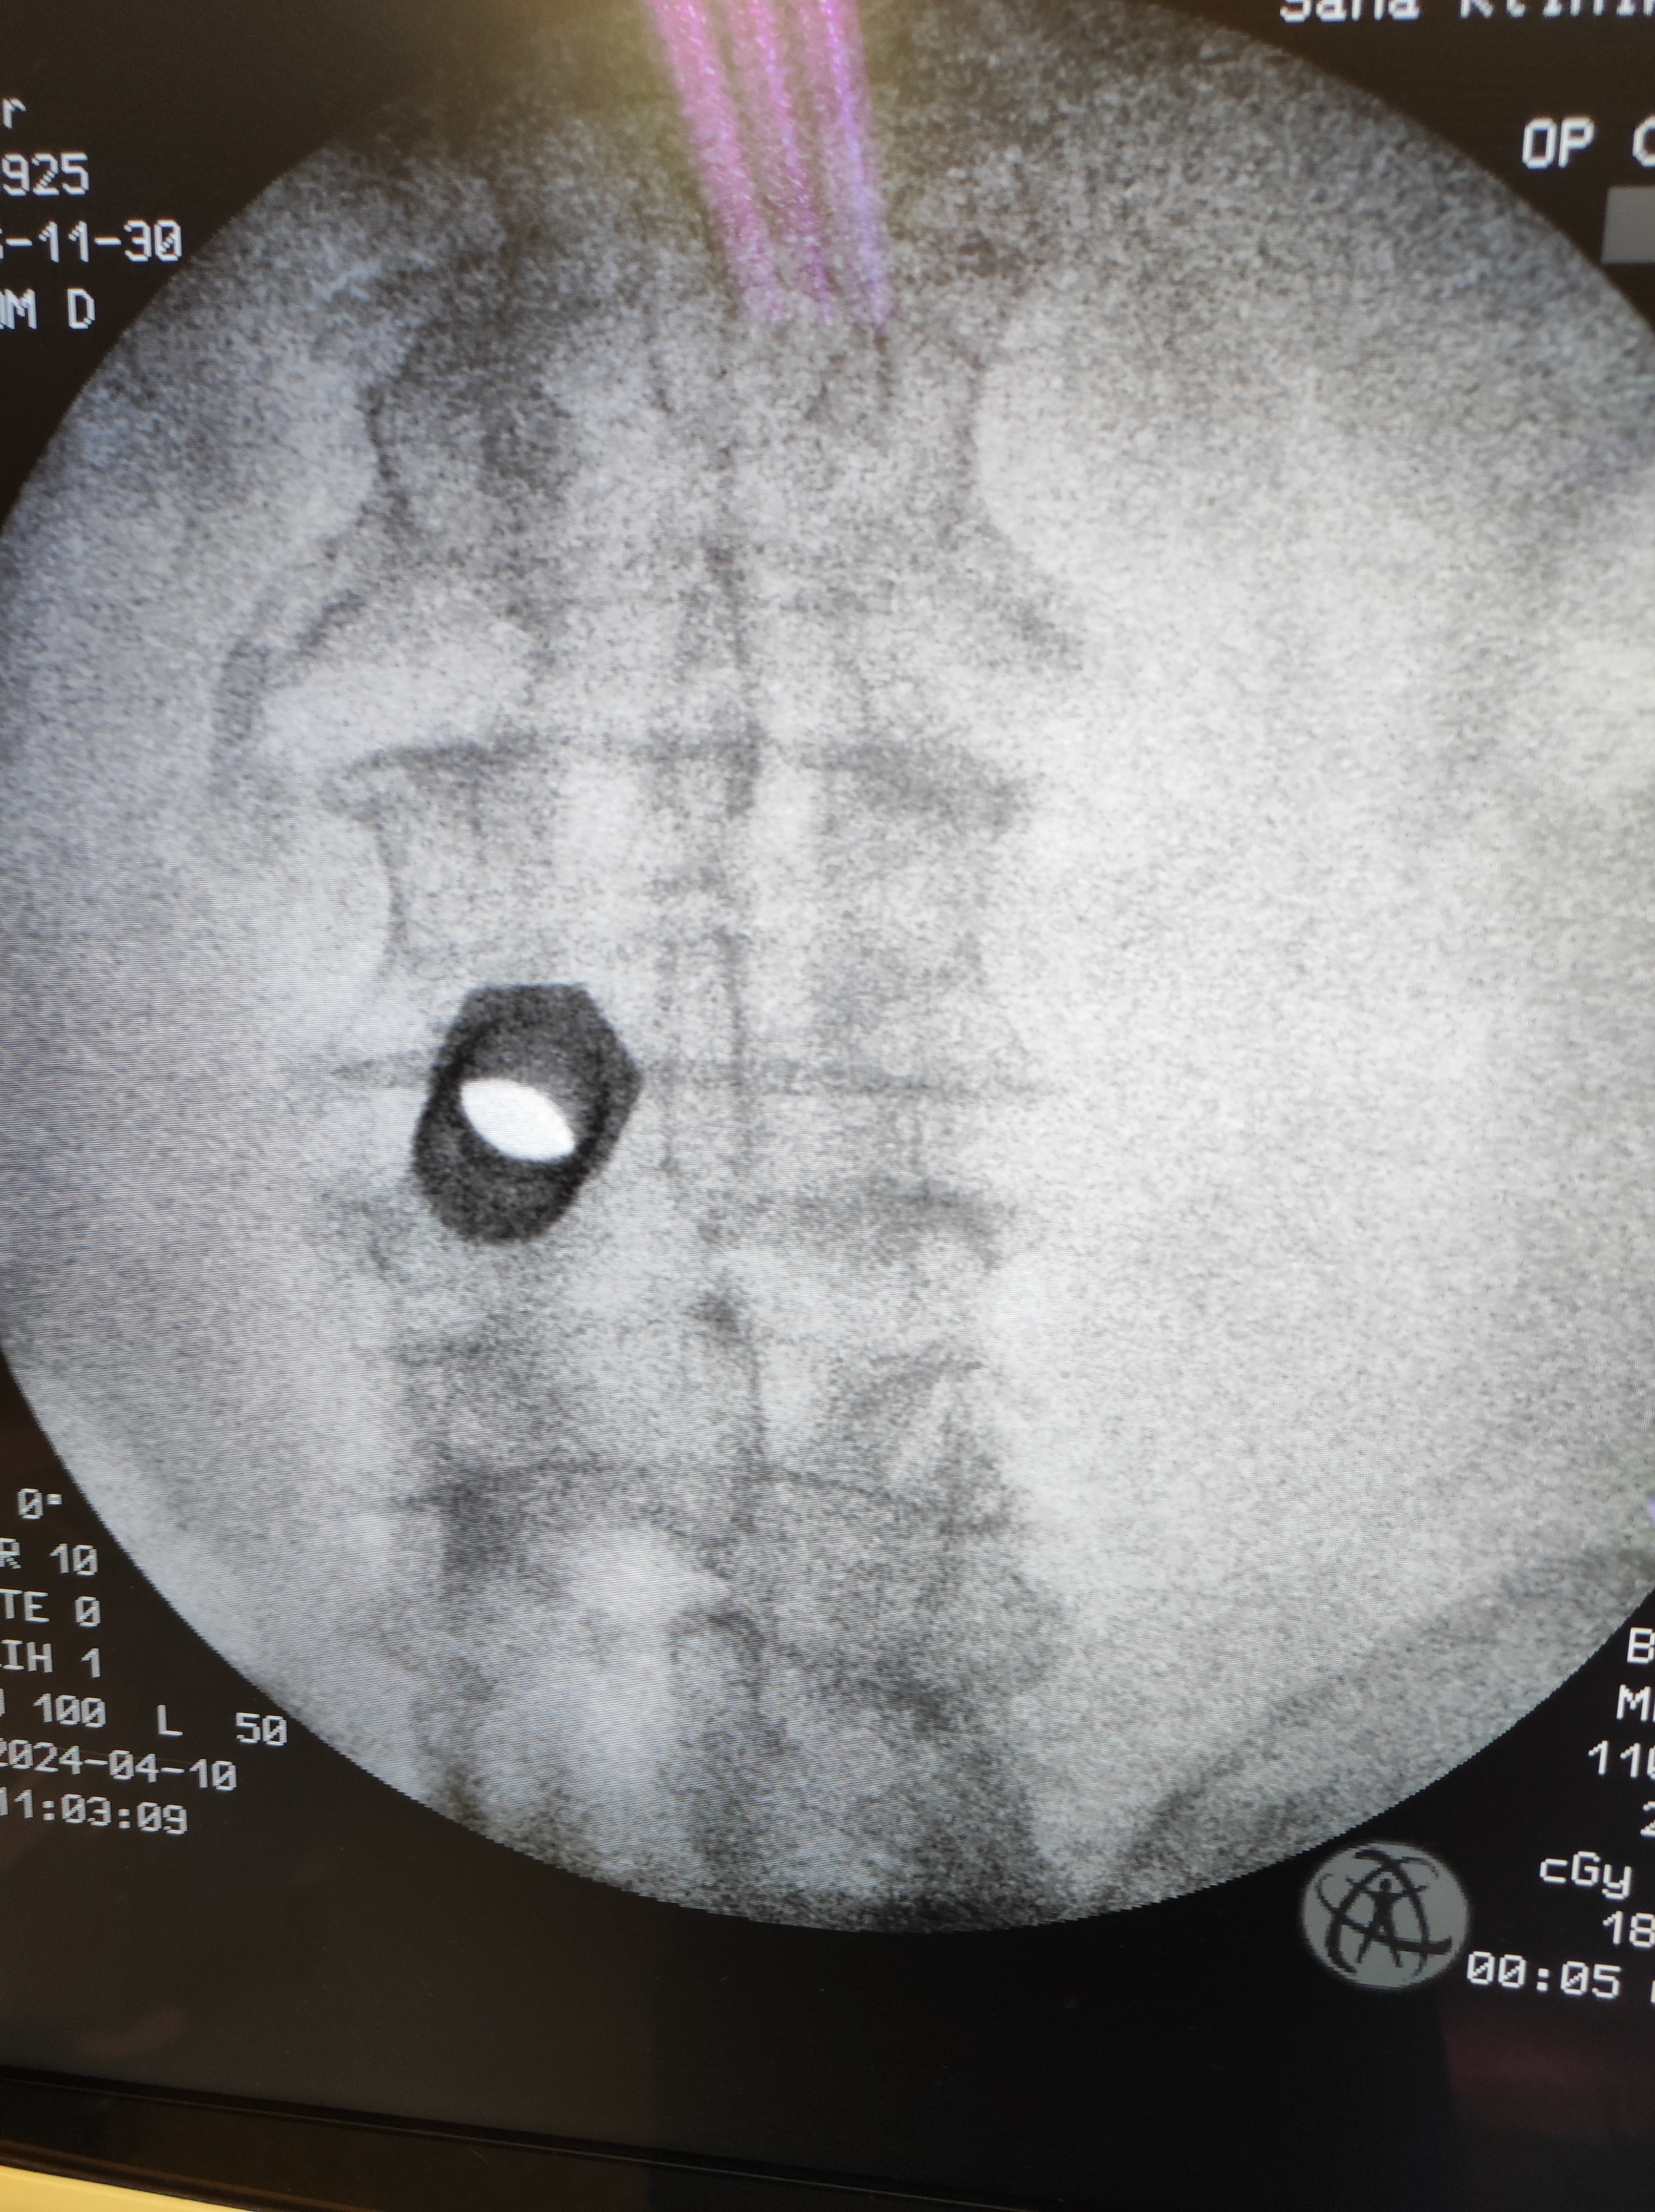

• Disectomía endoscópica

Disectomía endoscópica

• Discectomía Endoscópica

En la discectomía endoscópica, se realiza una pequeña incisión por la que se introduce un endoscopio (un tubo delgado con una cámara y luz) para visualizar y remover el material del disco herniado. Este método permite al cirujano trabajar con precisión y minimizar el daño a los tejidos circundantes.